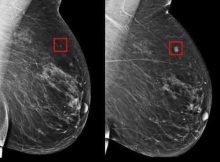

Los avances tecnológicos están revolucionando el campo de la medicina, y la inteligencia artificial (IA) ha demostrado ser una herramienta clave en la detección temprana del cáncer de